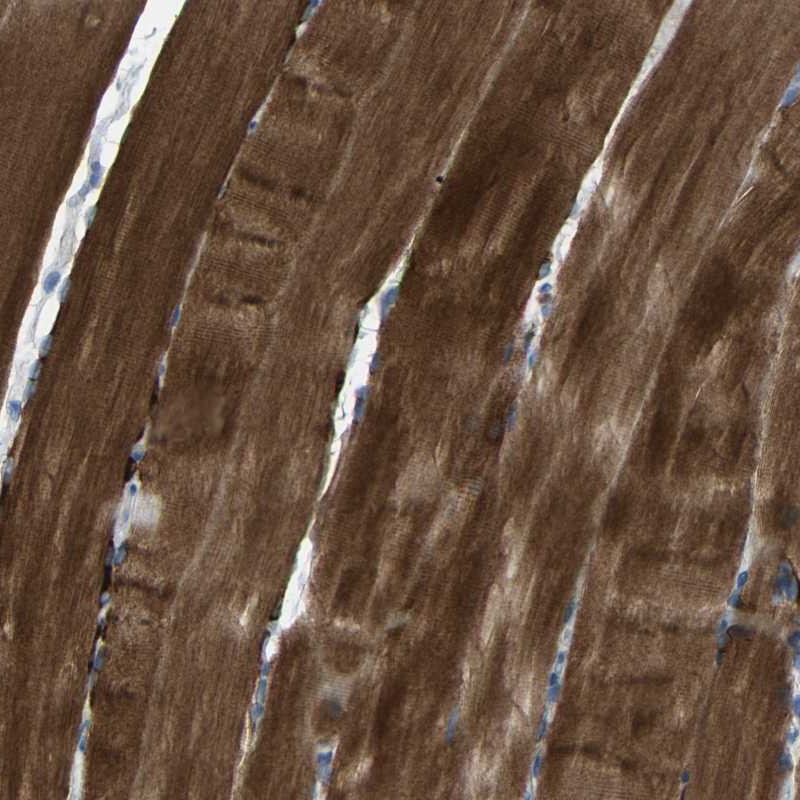

Immunohistochemistry analysis in human skeletal muscle and skin tissues using Anti-STBD1 antibody. Corresponding STBD1 RNA-seq data are presented for the same tissues.